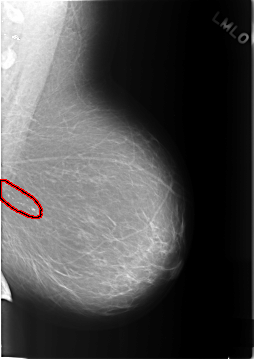

C_0317_1.LEFT_MLO

FILE: C_0317_1.LEFT_MLO.OVERLAY

TOTAL_ABNORMALITIES 1

ABNORMALITY 1

LESION_TYPE CALCIFICATION TYPE PLEOMORPHIC DISTRIBUTION CLUSTERED

ASSESSMENT 4

SUBTLETY 5

PATHOLOGY BENIGN

TOTAL_OUTLINES 1

BOUNDARY